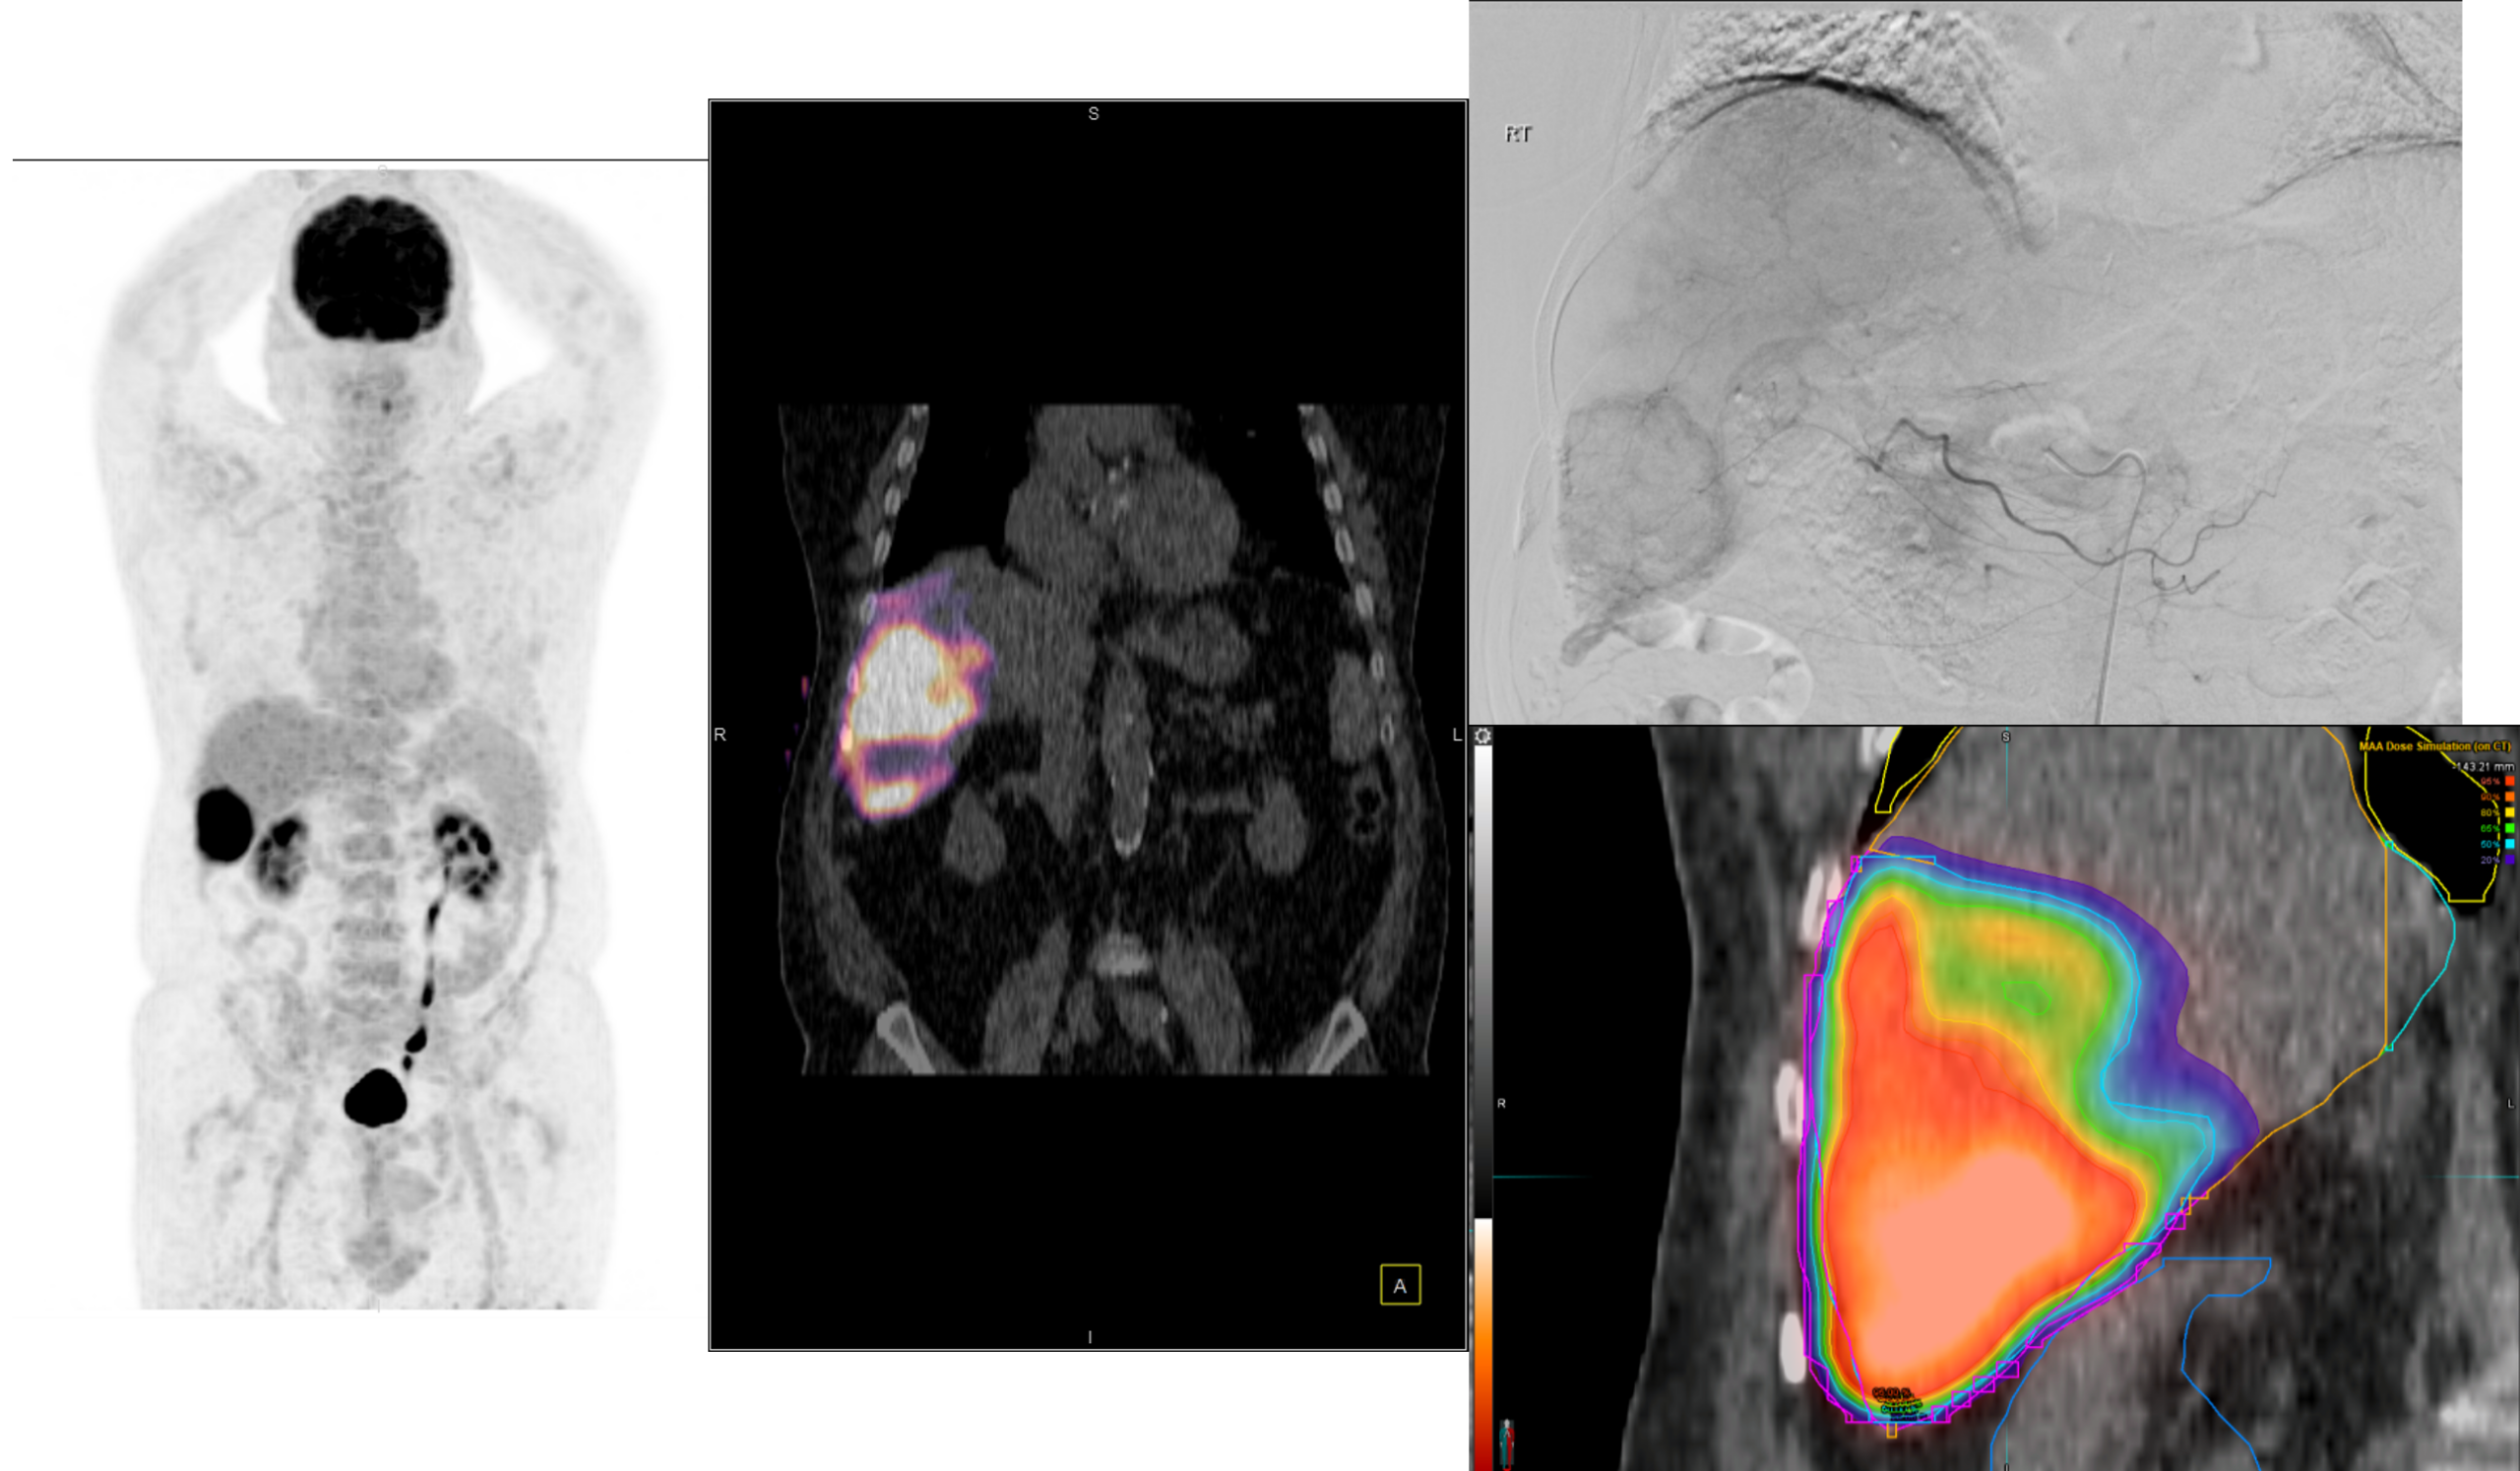

Η θεραπεία με Ύτριο-90 SIR-Spheres (Y-90) αποτελεί μια εξειδικευμένη τεχνική εκλεκτικού ενδοαρτηριακού εμβολισμού, η οποία στοχεύει αποκλειστικά τον όγκο μέσω των ηπατικών αγγείων, επιτρέποντας την εναπόθεση σωματιδίων που εκπέμπουν ραδιενέργεια τοπικά με ελάχιστη ακτινική επιβάρυνση στους υγιείς ιστούς. Η διαδικασία περιλαμβάνει λεπτομερή προθεραπευτικό αγγειογραφικό σχεδιασμό με αξιολόγηση της αγγειακής ανατομίας και χορήγηση ενός ιχνηθέτη για την ανίχνευση τυχόν διαφυγής (πχ. lung shunt), εξασφαλίζοντας μέγιστη ασφάλεια και εξατομίκευση. Η επιλογή της δόσης γίνεται πλέον με σύγχρονα υπολογιστικά μοντέλα δοσιμετρίας και εξειδικευμένα λογισμικά (όπως MIM ή SIR-TeX platform), τα οποία επιτρέπουν ακριβή αποτύπωση του όγκου της νόσου στο ήπαρ, υπολογισμό του πραγματικού tumor burden και εκτίμηση της απορροφούμενης δόσης τόσο στον όγκο όσο και στο υγιές ηπατικό παρέγχυμα. Μετά τη θεραπεία, πραγματοποιείται έλεγχος κατανομής της ακτινοβολίας (μέσω Bremsstrahlung SPECT/CT ή PET/CT), ενώ ακολουθεί στενή απεικονιστική και κλινική παρακολούθηση για την αξιολόγηση της ανταπόκρισης, την εκτίμηση τυχόν τοξικοτήτων και τον σχεδιασμό επόμενων βημάτων στην ογκολογική στρατηγική του ασθενούς. Πρόκειται για μια ιδιαίτερα αποτελεσματική θεραπευτική επιλογή σε πρωτοπαθείς ηπατικούς όγκους και σε ηπατικές μεταστάσεις, ειδικά όταν οι συμβατικές θεραπείες έχουν περιορισμένη αποτελεσματικότητα ή δεν είναι πλέον εφικτές.

Η θεραπεία με Lu-177 DOTATATE (PRRT – Peptide Receptor Radionuclide Therapy) αποτελεί μια από τις πλέον εξελιγμένες μορφές στοχευμένης ραδιονουκλιδικής θεραπείας για νευροενδοκρινείς όγκους του γαστρεντερικού και του παγκρέατος, αξιοποιώντας την υπερέκφραση των υποδοχέων σωματοστατίνης στους νεοπλασματικούς ιστούς. Η διαδικασία περιλαμβάνει τον ακριβή προσδιορισμό της έκτασης της νόσου μέσω Ga68 DOTATATE PET/CT, την επιβεβαίωση υψηλής έκφρασης υποδοχέων SSTR και στη συνέχεια τη χορήγηση του Λουτέσιο-177 DOTATATE, το οποίο δεσμεύεται εκλεκτικά στους ανωτέρω υποδοχείς. Η ενέργεια του β-εκπομπού Λουτέσιου επιτρέπει στοχευμένη κυτταροτοξική δράση μέσα στον όγκο, με ελάχιστη διασπορά σε υγιείς ιστούς. Η σύγχρονη πρακτική ενσωματώνει ειδικά λογισμικά δοσιμετρίας, που υπολογίζουν την απορροφούμενη δόση σε κρίσιμα όργανα (ήπαρ, νεφροί, μυελός) και την πραγματική δόση στον όγκο, επιτρέποντας εξατομικευμένο σχεδιασμό και βελτιστοποιημένη θεραπευτική στρατηγική. Μετά από κάθε κύκλο θεραπείας πραγματοποιείται απεικονιστικός έλεγχος, αξιολόγηση τοξικοτήτων και συνολική εκτίμηση ανταπόκρισης, καθοδηγώντας τις επόμενες φάσεις της θεραπείας. Το Lu-177 DOTATATE έχει αποδειχθεί εξαιρετικά αποτελεσματικό στη σταθεροποίηση και συχνά στη συρρίκνωση της νόσου, παρατείνοντας την επιβίωση και βελτιώνοντας σημαντικά την ποιότητα ζωής των ασθενών.